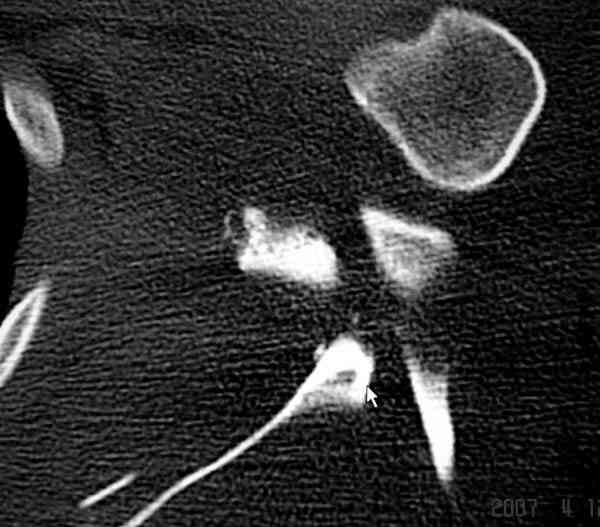

К-томографические и Трехмерные(3D)снимки крайне важны для определения внутрисуставных переломов и классификации.

Кроме анатомической классификации, переломы лопатки делятся на стабильные и нестабильные, внутри- и внесуставные и с вовлечением суставной поверхности.

Также показания к оперативному вмещательству на лопатке появляются, когда смещения суставной поверхности медиально 9 и более мм и при угловом смещении суставной поверхности 40 и более градусов.